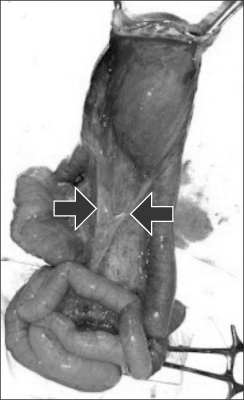

A full term 2.5 kg male baby was referred soon after birth as a case of omphalocele. The neonate had passed urine and small amount of meconium. The cry, tone and activity of the baby was good. On abdominal examination, there was a large sac 6×5 cm with a narrow pedicle of 2 cm (

Fig. 1). The nasogastric tube was draining bile. An abdominal radiograph revealed few bowel loops inside the sac (

Fig. 1Hernia of umbilical cord with a narrow pedicle.